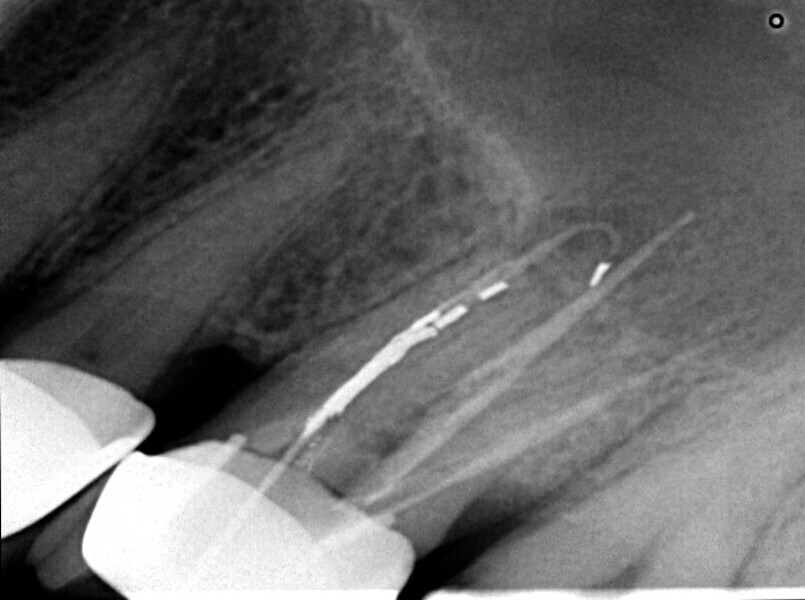

Maxillary sinus and root canal therapy complications